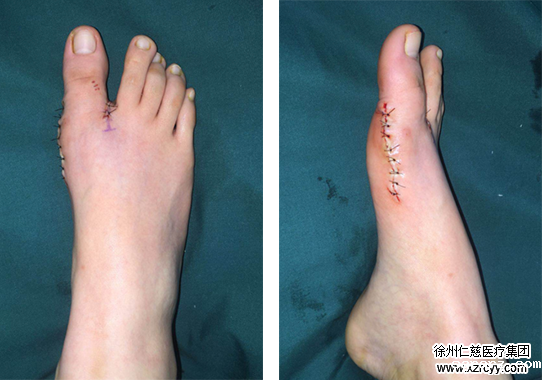

经过检查,小旭的右足踇指自跖趾关节向外侧偏斜移位,踇外翻角约37°,跖间角约15°,第一跖骨头内侧膨大,踇囊形成。采取Chevron+akin截骨进行踇外翻矫正手术,于是对小旭安排了住院准备手术。

术后

苏省医生配合曹主任对小旭的踇外翻进行了手术,术中切除跖骨头骨赘,对第一跖骨远端和近节跖骨做截骨。术后不久,小旭就可以下床行走,疼痛消失。